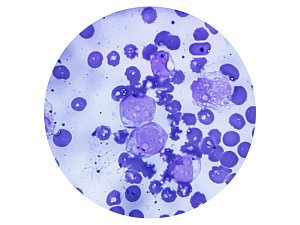

билиарный цирроз

Первичный билиарный цирроз – заболевание печени, носящее аутоиммунный характер. Начинается первичный билиарный цирроз с бессимптомного деструктивного негнойного холангита, который принимает хронический характер течения, приводит к развитию длительного холестаза и как результат к циррозу.

Распространенность заболевание варьируется от 20 до 150 случаев на 1 млн. населения. В структуре смертности от циррозов составляет 2%.

Клинически ПБЦ проявляется кожным зудом, мальабсорбцией, остеопорозом и желтухой. Лечение: симптоматическое, направленное на устранения клинических проявлений и патогенетическое, единый подход к которому отсутствует.

Рекомендовано использование Урсодезоксихолевую кислоту, эффективность которой доказана.